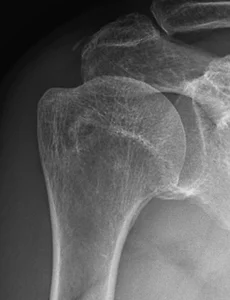

Shoulder61 Proximal humerus fracture Proximal humerus fracture65 years old female patientTripping over a rope Pre-op Post-op Materials : Philos plate(AO synthes) & 2.4 mm mini-plate(AO synthes) 제일 처음 cortical screw를 고정할 위치에 Fx. line이 존재하여미리 2.4 mm mini-plate 로 OR & fixation을 하여어느 정도 stability를 만든 후, Philos plate를 apply 함. 2026. 1. 1. Comminuted clavicle mid-shaft fracture Comminuted clavicle mid-shaft fracture36 years old male patient Pre-op Post-op Materials : AO synthesnew version, 2.7 mm clavicle platelag screw, 2.4 mm mini-screw 쇄골 골절을 쉽게 생각하면 절대 안됩니다 2025. 6. 23. Humerus surgical neck fracture Humerus surgical neck fracture 52 years old female patientSlip down injury in the bath room Pre-op Post-op 2024. 8. 20. Humerus neck fracture(ORIF) Fx humerus neck Lt. 35 years old male patient 자전거 타고 가다가 차와 충돌하여 LOC (+) Pre-op Post-op Product : AO synthes (Philos plate)Delto-pectoral approach 하여 biceps tendon의 just lateral에약간 비스듬히 Philos plate를 대면 정확한 고정이 이뤄집니다. 2024. 6. 22. 어깨의 인대 손상 격렬한 운동을 하다 보면 어깨 관절을 다치기가 아주 쉽습니다. 그러면 어깨 관절에 피하 출혈(멍듦)이 생기기도 합니다. Skin bruise of shoulder joint 어깨 관절의 인대는 상당히 강하며 뼈와 뼈를 연결하는 구조물이기 때문에 우리 몸속 깊숙히 있습니다. 어깨 관절의 인대(ligament) 인대 손상의 확인은 MRI 검사로 합니다. 2021. 11. 6. Frozen shoulder(동결견) 정상적인 어깨 관절은 견갑-흉곽 운동(Scapulo-thoracic motion)에 의해서 복합적으로 이뤄지게 됩니다. 어깨 통증으로 평소 사용하는 앞쪽 근육이 아닌 잘 사용하지 않는 어깨 뒷쪽 근육부터 굳기 시작을 합니다. 그래서 처음에는 어깨의 내회전(열중 쉬어 자세)이 안됩니다. '동결견'은 어떤 이유(당뇨, 경추부 추간판 탈출증, 골절 등)로 인해 '어깨 관절의 운동 범위가 감소한 경우'로 정의 합니다 '동결견'의 병태 생리는 '어깨 관절의 비화농성 염증(non-pyogenic inflammation) 및 관절막의 섬유화(fibrosis)' 입니다 최근에는 '경추부 추간판 탈출증'으로 인한 '이차성 동결견'이 증가하는 양상을 보이고 있습니다 '오십견'이라는 병명은 정확한 병명은 아닙니다 '동결견'.. 2021. 1. 10. Proximal humerus fracture(Hemi-arthropalsty) Proximal humerus fracture 88 years old female patient with severe OA change Pre-op Post-op 2020. 2. 2. Cuff tear arthropathy shoulder Rt. Cuff tear arthropathy shoulder Rt. 70 years old male patient 회전근개 파열 후 오랜 시간이 지나 '관절염'이 발생한 경우입니다. 2019. 11. 18. Calcific tendinitis shoulder both Calcific tendinitis shoulder both 46 years old female patient 2019. 9. 4. 이전 1 2 3 4 ··· 7 다음